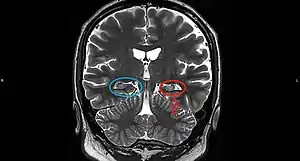

On a MRI T2-weighted or T2–fluid‐attenuated inversion recovery (FLAIR) scan, hippocampal sclerosis appears as an increased signal, smaller sized (atrophic) hippocampus with a less well-defined internal structure.[2] Increased signal means that hippocampal sclerosis will appear brighter on the MRI image. Less well-defined internal structure means the expected sharp boundaries between hippocampal gray and white matter structures are absent.[2] The total volume of the hippocampus is also reduced.[2] The reduced volume arises from neuronal cell loss, and increased signal arises from gliosis.[2]